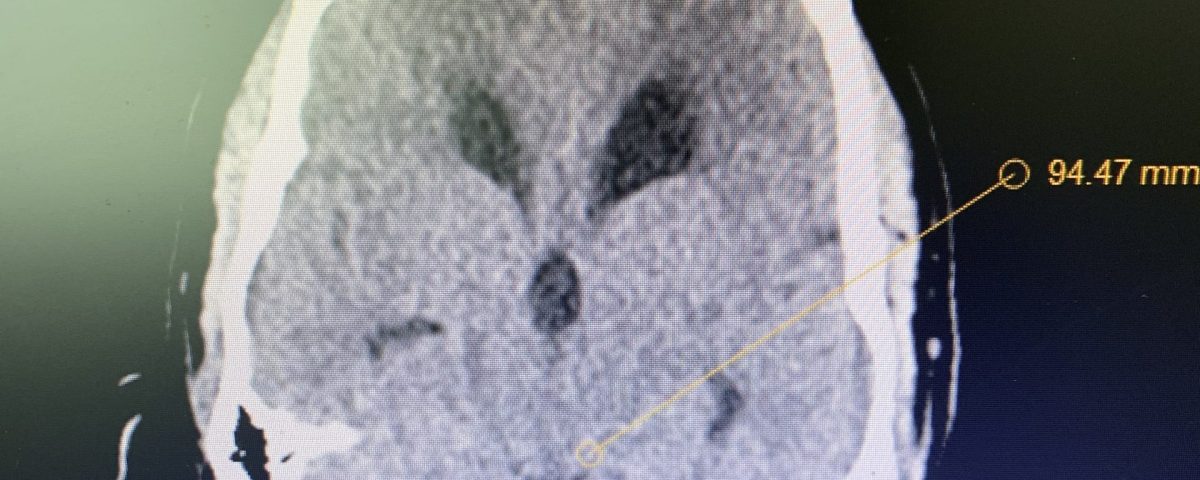

Figure 1B,C: Pre-operative CT images.

Prior to shunting, a head CT was obtained and the head CT in addition to documenting a patten of obstructive hydrocephalus suggested a possible mass lesion compressing the aqueduct at its inferior aspect. Figure #1 demonstrates the hydrocephalus and the possible lesion. A decision was made at this point that the patient had obstructive hydrocephalus that was now symptomatic and he was taken for a laparoscopic-assisted ventriculoperitoneal shunt.